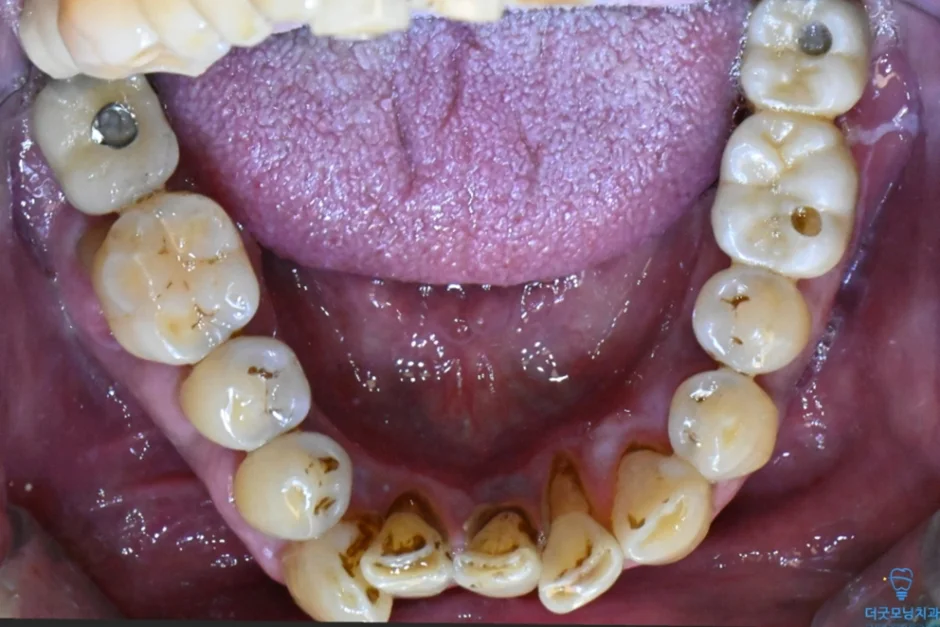

해당 환자분은 과거 치과 치료 경험이 좋지 않아 치과 공포증이 있으셨고, 치료 자체에 대한 두려움이 크셨습니다. 치료를 오랫동안 미루셨고, 그 사이 구강 상태가 많이 악화된 상태로 내원하셨습니다.

먼저 파노라마 엑스레이와 CT를 통해 구강 전체 상태를 확인하였습니다.